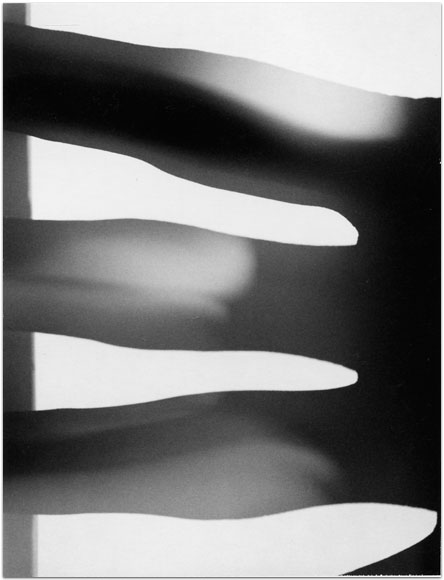

- Itis

- 2004

- 3.25″ × 4.25″

- Photographic montages of my hands & health paraphernalia on Polaroid Type 664 & 669 Film using a Daylab Printer.

- Frustrated by a lack of mobility and severe pain with my fingers, unable to accomplish any task requiring joint dexterity,

I noticed piles of health related papers strewn around. I layered these in a slide printer without removing

my hands, enlarging both onto the film.